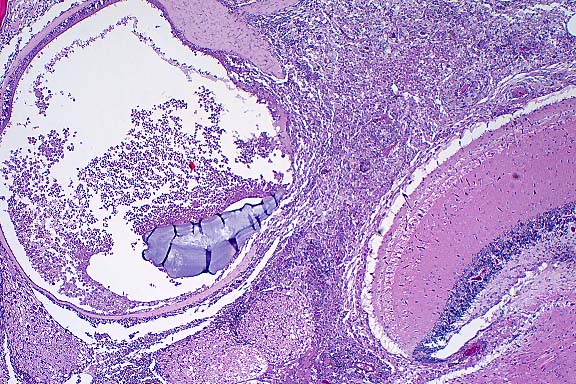

10x

obj

- Case 8-4. Kidney. Hematopoietic cells are largely

replaced by hemorrhage and congestion which expands the interstitium

and separates tubules.

40x

- Case 8-4. Kidney. Multifocally, tubular epithelium

is necrotic.

- Case 8-4. Multifocally and randomly throughout the

hepatic parenchyma, there are pale zones of hepatocellular necrosis

(loss of cell detail, karyolysis, pyknosis, & cell loss).